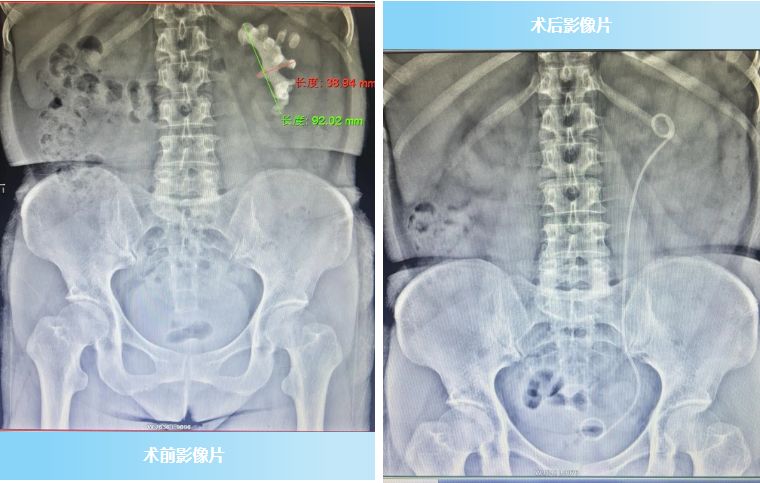

患者李女士,55岁,被左肾结石困扰3年余,近期因反复出现左腰部胀痛入院。完善相关检查发现:左肾多发铸形结石,最大38mm*90mm,伴有肾积水和感染,同时还存在右肾萎缩、慢性肾功能不全的情况,病情复杂棘手。为挽救患者肾脏,彻底清除结石,泌尿外科专家团队迅速对患者病情综合评估,为其制定了个性化诊疗方案,决定对其实施“左PCNL术+经皮左侧输尿管支架置入+经尿道右侧输尿管支架置入术”。

手术由泌尿外科曾庆春主任与其带领的泌尿外科手术团队共同完成。手术中,曾庆春主任凭借丰富经验和娴熟技术,在全麻下精准操作:先通过尿道置入肾镜处理输尿管情况,再于超声引导下经皮穿刺左肾中盏,建立通道后利用钬激光将铸形结石击碎并取出,同时置入输尿管支架和肾造瘘管保障引流。整个手术用时约160分钟,过程顺利,术中出血仅约50ml,患者术后恢复良好,顺利康复出院。